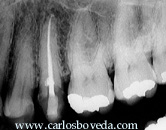

Nos

llamó la atención la imagen

radiopaca que se evidencia periapical al

primer molar. En el momento analizamos con

detalle su examen radiográfico

periapical completo e indicamos la toma de

una radiografía panorámica

dental-sinusal.

Este

examen radiográfico

periapical se encuentra

digitalizado en dos segmentos. El

primero contiene la zona

posterior derecha y el segundo

contiene la zona anterior y la

zona posterior izquierda. Haga

click sobre el segmento de la

imagen que desee agrandar. La

radiografía

panorámica fue tomada

posterior al tratamiento

endodóntico del tercer

molar inferior derecho. Haga

click sobre ella si la desea ver

a mayor

resolución.

Las evaluaciones radiográficas

evidencian la unilateralidad de la imagen

radiopaca periapical a la raíz

distal del primer molar inferior derecho.

imágenes radiográficas

sugieren una disminución del

espacio pulpar del primer molar inferior

derecho, así como una posible

alteración de la arquitectura

apical en su raíz

distal.